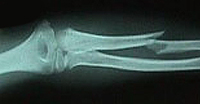

Fracturas de cúbito y radio

Las fracturas del cúbito y radio son las más frecuentes de la infancia y tienen lugar generalmente por caídas en lugares de recreo y durante la práctica deportiva. En la edad adulta los accidentes de tráfico y los deportes de contacto son las causas más frecuentes de lesión a este nivel. El tratamiento depende del tipo de fractura y grado de desplazamiento. Se realizará tratamiento conservador siempre que la fractura lo permita relegando el tratamiento quirúrgico a aquellas fracturas difícilmente estabilizables mediante escayola.